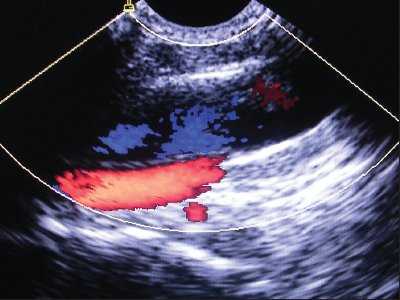

Рис. 3. Нормальное расположение и размеры внутренней яремной вены и сонной артерии при исследовании в продольном сечении (сонная артерия находится глубже внутренней яремной вены).